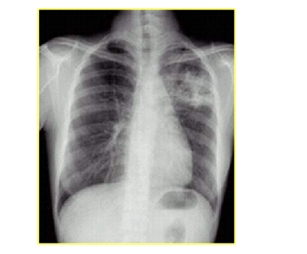

三、肺结核病

结核关键词:低热、盗汗、乏力、体重减轻

影像学关键词:肺尖、空洞、钙化、哑铃

| 肺结核类型 | 影像学表现 |

| 局限性斑片状模糊影 | 好发于上叶尖后段及下叶背段 |

| 干酪性肺炎 | 肺段或肺叶实变,呈大片致密影,边缘模糊,密度不均,急性空洞表现为“虫蚀样” |

| 结核性空洞 | 多数空洞壁较薄,洞壁内、外缘较光滑,空洞内一般无液平,空洞周围常有卫星灶 |

| 支气管播散病变 | 支气管分布的斑点状、斑片状阴影 |

| 血行播散病变 | 散在于两肺野、分布较均匀、密度和大小相似的粟粒状阴影;亚急性和慢性病变粟粒大小和密度不一 |

| 增殖性病变 | 斑点状高密度影,常排列成“花瓣”,边界清楚,无融合趋势 |

| 结核球 | 边缘清楚的类圆形阴影,密度较高,内常有钙化,周围可见卫星灶 |

| 原发性结核灶 | 哑铃状病灶 |